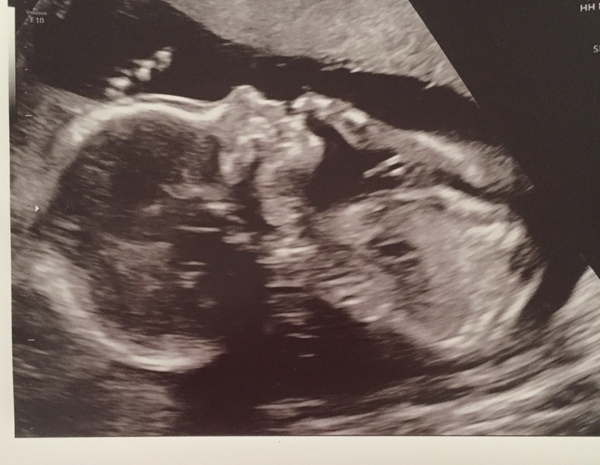

Minkies13 · 07/04/2018 11:08

Hi ladies,

I haven't posted in such a long time. I'm not on the Facebook group either. I finally made it to 20 weeks.

We had a private scan done at 17 weeks because I was going to be overseas for my anomaly scan so I had to cancel it. I'm going privately when I get back.

This photo was taken at 17+4

Little girl.

Minkies what a fantastic photo!

I know I sound like a total grandma but I am so amazed by how detailed the scans are now. I dug out DS's old 20 week scan from 2008 today and the difference really is astounding. I'll do a comparison when we get one.

I've found that the photos from the private scans are so much clearer than the NHS scans...

But you're right, the detail is great